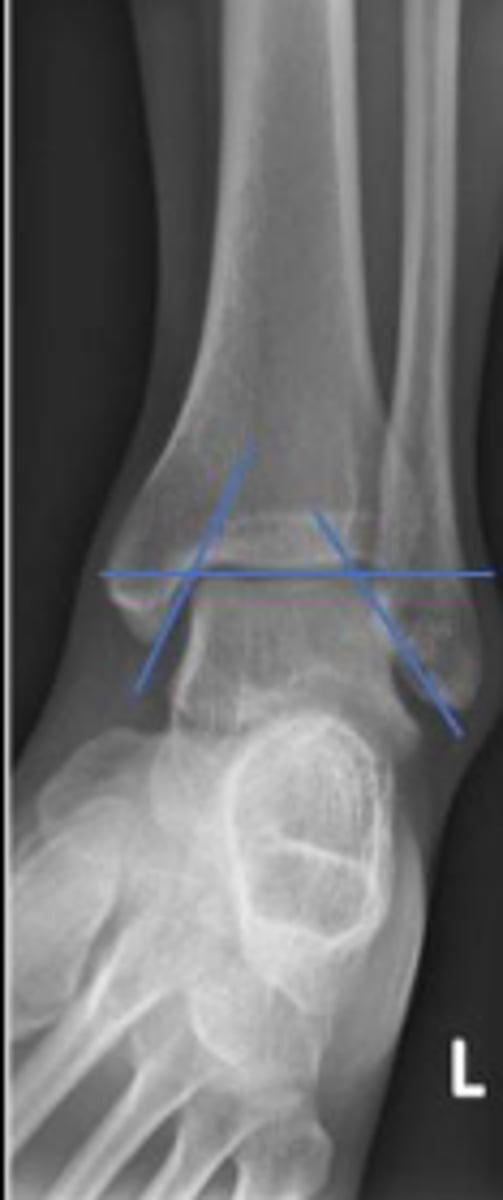

Axial relationship of the ankle

What is the overarching name of the assessment?

Tibial angle & fibular angle

What are the 2 components of the assessment?

Tibial angle

What is the name of the assessment?

Yes

Is the assessment within normal limits?

Fibular angle